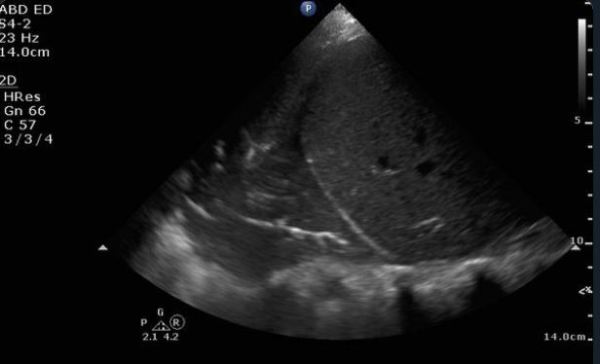

Lung and Diaphragm Ultrasound as Predictors of Success in Weaning from Mechanical Ventilation